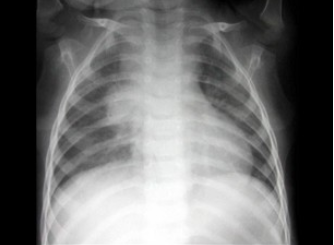

患者,男,3岁,突发左侧胸痛伴呼吸困难3小时入院,如图所示,最可能的诊断为()

患儿,男,1天,生后呼吸困难,羊水见胎粪污染,如图,最可能的诊断为()

A.新生儿肺炎

B.新生儿湿肺

C.新生儿肺出血

D.新生儿呼吸窘迫综合症

E.胎粪吸入综合征